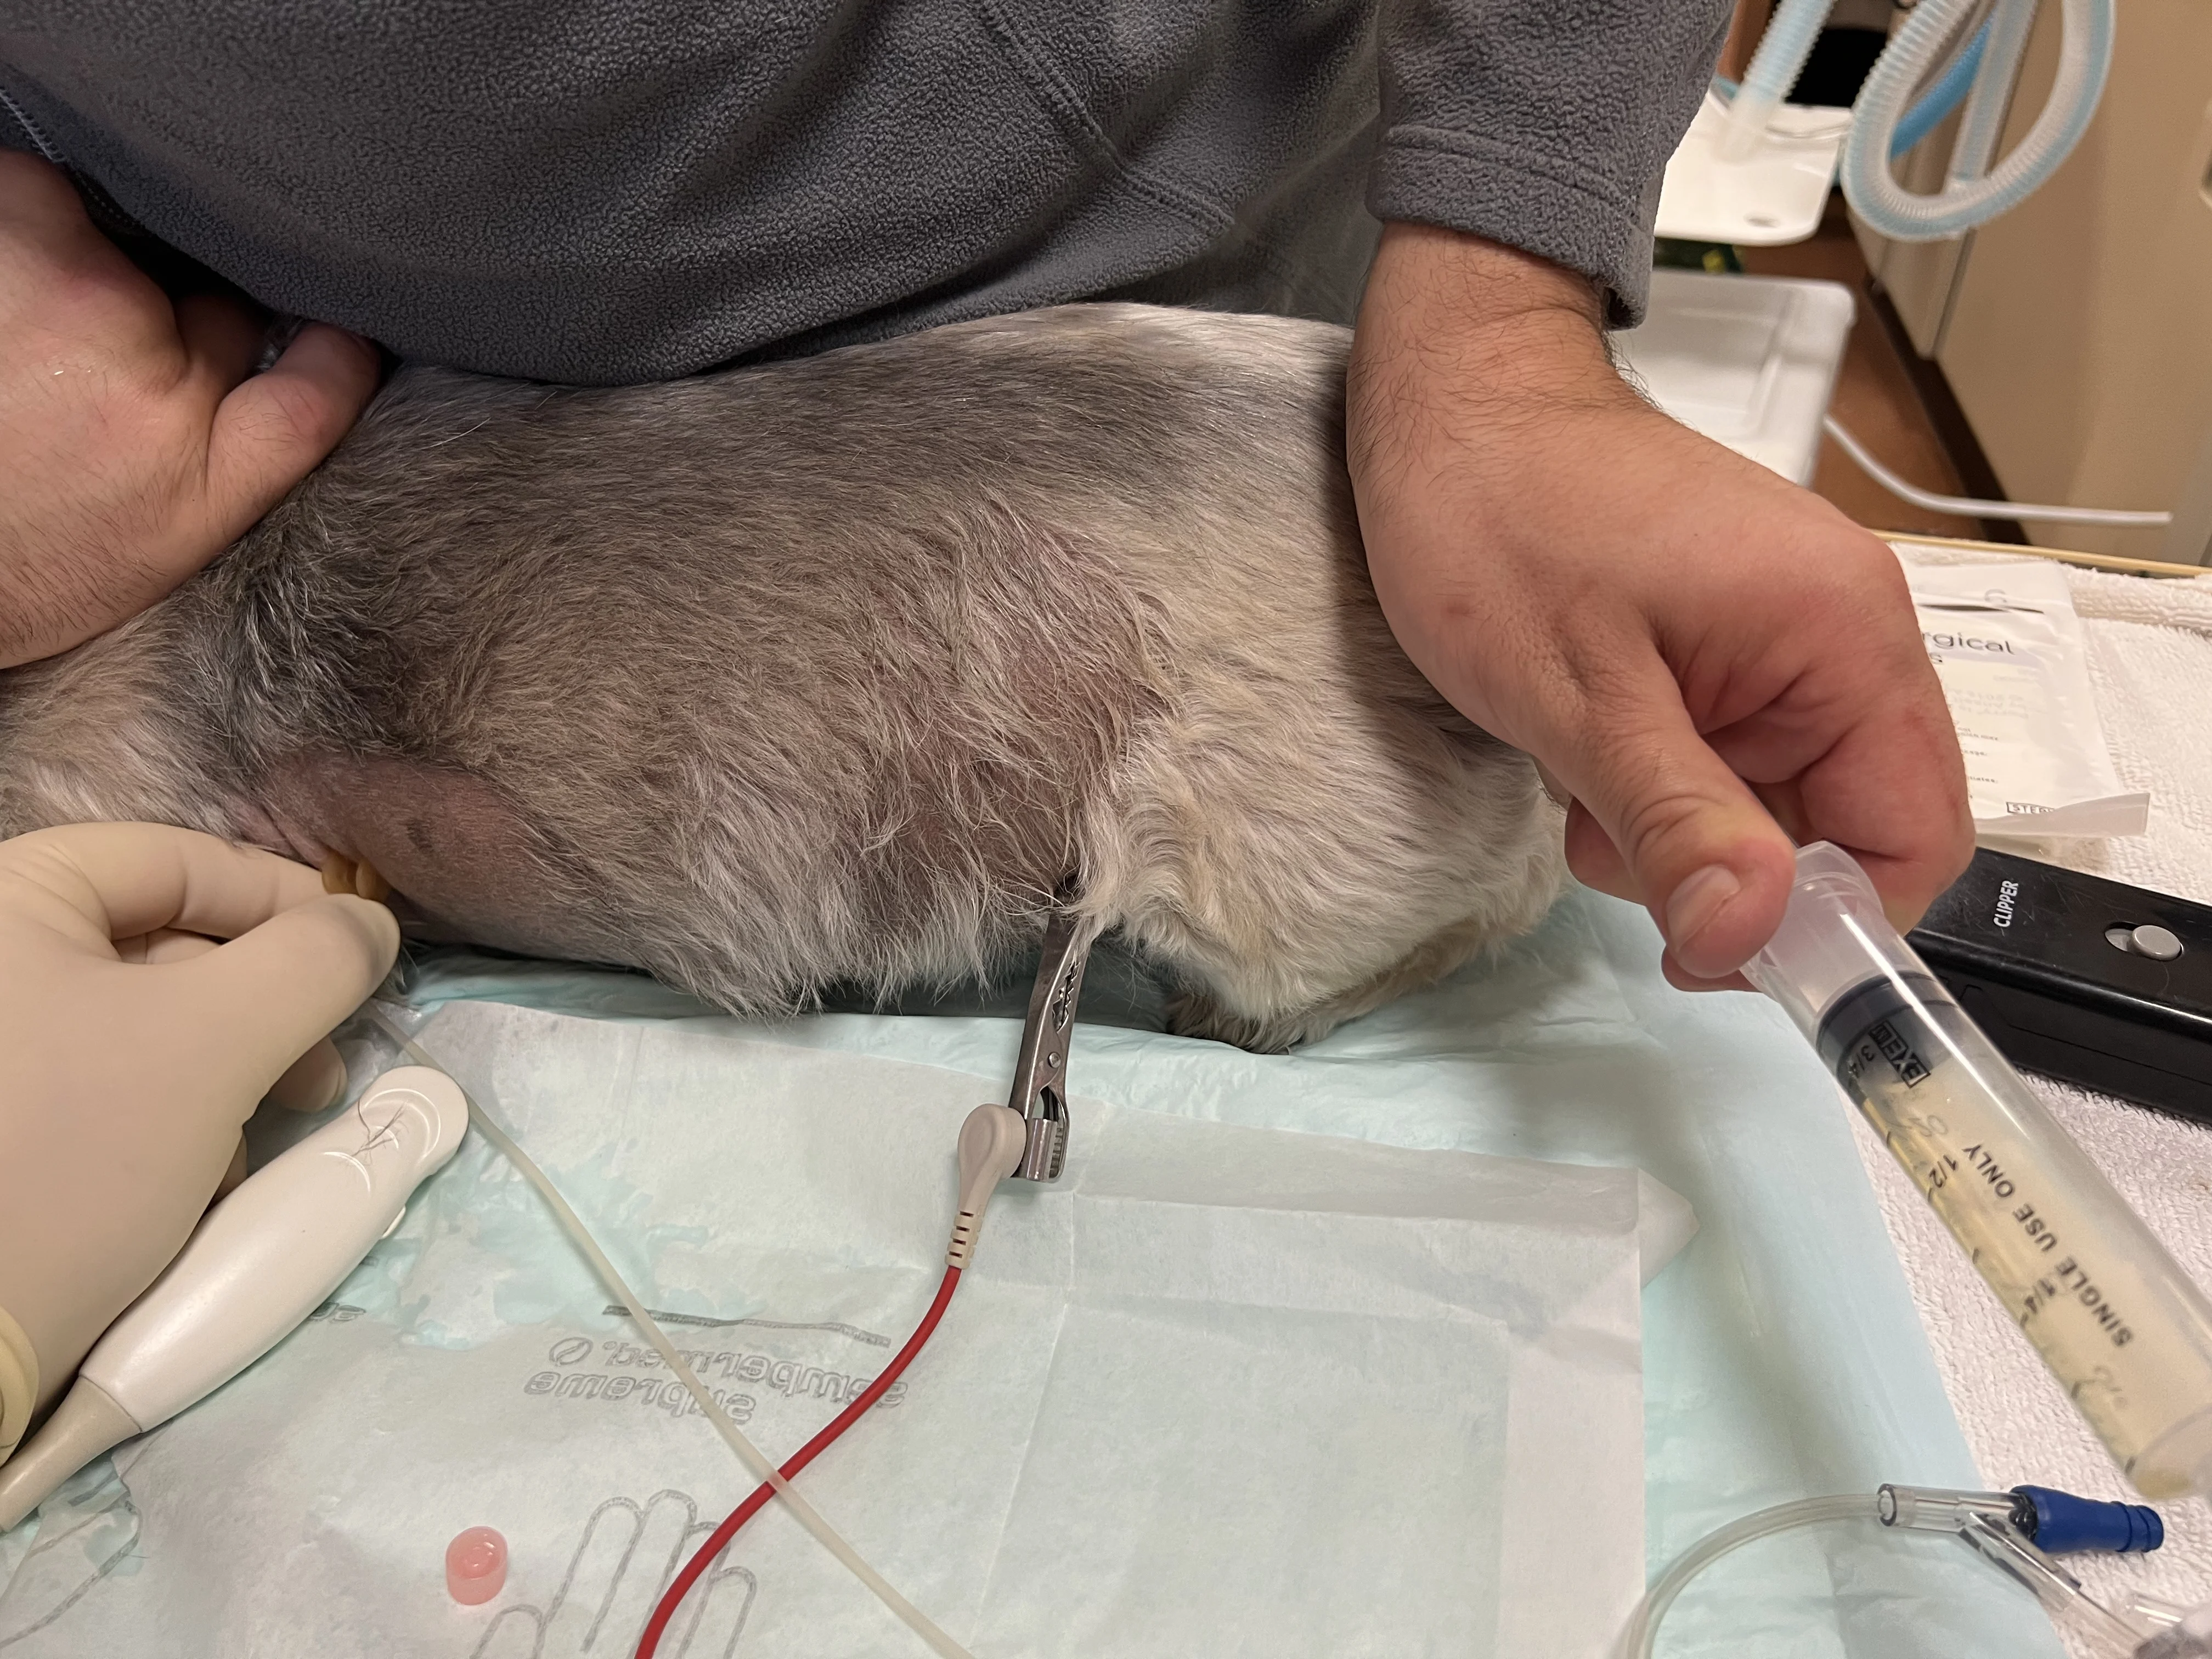

Provide sedation and/or oxygen therapy as indicated. Connect ECG leads (if available). Place the patient in the most comfortable and least stressful position (sternal recumbency is most effective in the author’s experience, but the patient can also stand, sit, or be in lateral recumbency).

Three staff members are typically needed to perform thoracocentesis: one to restrain the patient, one to place and stabilize the needle, and one to operate the syringe for fluid collection. Sedation can ease patient stress and discomfort and provide appropriate restraint. In the author’s experience, butorphanol (0.2 mg/kg IV, SC, or IM) with or without midazolam (0.2 mg/kg IV, SC, or IM) can provide adequate, safe sedation in patients in respiratory distress.16,20

Oxygen therapy can be provided via flow-by tubing or an oxygen mask (if tolerated).

Step 3: Prepare the Skin

Clip the fur and aseptically scrub the skin around the needle insertion site(s) while wearing nonsterile gloves.

Step 5: Insert the Needle

Wearing sterile gloves, insert the needle at the cranial aspect of a rib (to avoid the intercostal vessels) with the bevel facing up and at a 45-degree angle to the body wall. Slowly advance the needle until it passes through the body wall. Back the needle out slightly if a gentle scraping sensation is felt on the needle tip, as the needle may be rubbing the lung. If using an over-the-needle catheter, remove the stylet and reattach the catheter to the extension set.